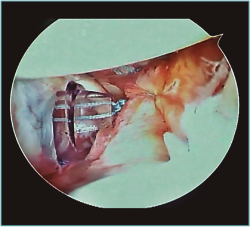

A excepción de los pacientes con significativos déficit óseos o recidivas con una mala calidad de tejido capsular, realizamos una técnica de reparación artroscópica. Operamos siempre con el paciente en decúbito lateral, con anestesia regional y general. Utilizamos siempre 4 portales instrumentales y un portal superior visual de exploración. Comenzamos nuestras cirugías con un portal de visión posterosuperior y un portal anterior de trabajo. Dependiendo de los hallazgos, realizamos las plicaturas capsulares que sean necesarias. En repetidas oportunidades encontramos hiatos intracapsulares, como por ejemplo entre el ligamento glenohumeral medio y superior, o laxitudes capsulares centrales, tratando los mismos con suturas de superior a inferior para generar una plicatura similar al capsular shift, incluso aumentando el espesor capsular (Figura 3). Luego de reparar estos defectos capsulares, seguimos nuestras plicaturas desde posterior, a través de un portal posteroinferior accesorio, colocando un anclaje con doble sutura, realizando la reparación y/o plicatura del haz posterior del ligamento glenohumeral inferior y achicando el receso inferior agresivamente siempre con anclajes de doble sutura (Figuras 4 y 5). Luego pasamos a un portal superior de visualización, dedicamos el tiempo necesario a liberar todo el labrum anteroinferior, despegando la cápsula anterior y el labrum del subescapular para movilizar e incluso acortar la cápsula, en ocasiones resecando parte de la misma para mejorar la plicatura; siempre utilizamos una sutura de tracción anterosuperior por fuera de la cánula para traccionar el tejido. Para poder llegar lo más cercano a hora 6, el primer anclaje anterior lo colocamos por un nuevo portal percutáneo transubescapular, utilizando arpones doble sutura, usando el primer par de suturas para llevar la cápsula y el labrum hacia la glena realizando sobre esta una sutura doble de tipo colchonero para mejorar la aposición capsular (Figura 6). Luego colocamos en la mayoría de los casos 2 anclajes más para terminar la reparación, en general 4 arpones. De haber un intervalo de rotadores amplio, no vacilamos en cerrarlo con suturas (Vídeo anexo).

Figura 6. Hombro izquierdo. Se visualiza portal transsubescapular para llegar a hora 6.